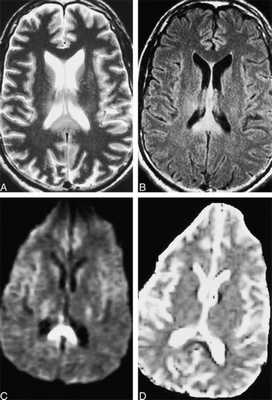

ДАП при МРТ головного мозга выглядит чаще всего как разбросанные по белому веществу очаги разных размеров (до 15 мм). В самом раннем периоде ДАП хорошо виден на диффузионно-взвешенных МРТ, в виде гиперинтенсивных очагов. Т1-взвешенные МРТ головного мозга помогают дифференцировать ДАП с микрокровоизлияниями.На Т2-взвешенных МРТ головного мозга очаги ДАП гиперинтенсивны, локализуются типично в валике мозолистого тела, кортико-медуллярных переходах височных и теменных долей.

МРТ головного мозга. А- Т2-взвешенная аксиальная МРТ, В - МРТ типа FLAIR, C - диффузионно-взвешенная МРТ, D- карта диффузии (ИКД). ДАП в подострой стадии.

МРТ головного мозга при выявлении ДАП придается важное прогностическое значение. Количество и размеры очагов ДАП на МРТ головного мозга коррелируют со степенью поражения и длительностью комы. Определенные надежды возлагаются и на применение диффузионно-тензорных МРТ а также МРТ трактографии.